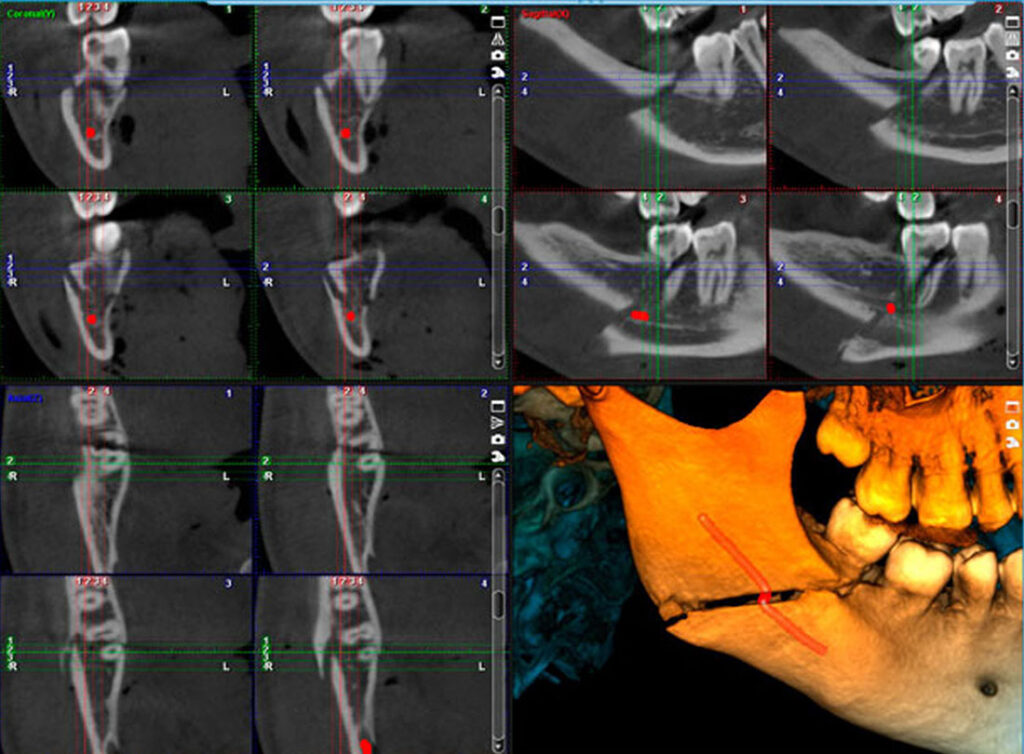

Endodontic imaging mode

(Veličina polja prilagodljiva uzrastu i veličini pacijenata)

• Malo polje Ø40×50 mm

• Veoma visoka rezolucija, veličina voxela 75 µm – perfektna slika za fine anatomske detalje

Primena CBCT snimka u oblasti endodoncije:

• Procena komplikacija endodontskog lečenja

• Dg periapikalne patologije

• Komplikovan sistem kanala korena

• Utvrđivanje zakrivljenosti kanala korena

• Dg traume – fraktura korena, alveolarnog nastavka, luksacije

• Lokalizacija resorpcije korena

• Određivanje tačne lokalizacije apexa korena u prehirurškom planiranju

• Tačne mere

Malo polje Ø40×50 mm velicina voksela 150 µm

Malo polje Ø40×50 mm, velicina voksela 75 µm